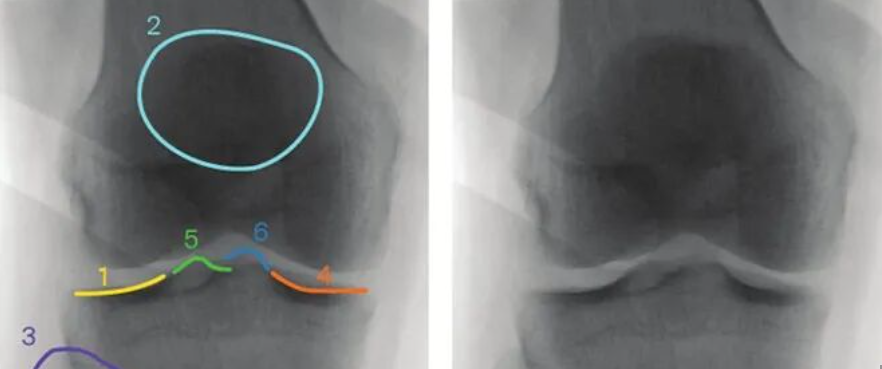

伸直型骨折:最常见,多为间接暴力致伤。1814年由A.Colles详加描述。跌倒时腕关节处于背伸及前臂旋前位、手掌着地,暴力集中于桡骨远端松质骨处而引起骨折。骨折远端向背侧及桡侧移位。儿童可为骨骺分离;老年人由于骨质疏松,轻微外力即可造成骨折且常为粉碎骨折,骨折端因嵌压而短缩。粉碎骨折可累及关节面或合并尺骨茎突撕脱骨折及下尺桡关节脱位。

巴尔通骨折:系指桡骨远端关节面纵斜型骨折,伴有腕关节脱位者。由J.R.Barton1838年首次描述。跌倒时手掌或手背着地,暴力向上传递,通过近排腕骨的撞击引起桡骨关节面骨折,在桡骨下端掌侧或背侧形成一带关节面软骨的骨折块,骨块常向近侧移位,并腕关节脱位或半脱位。

满意复位的标准为:桡骨短缩小于2~3mm,桡骨远端关节面为掌倾而非背倾,尺偏角恢复接近或达到20°,无粉碎性骨折片合关节面不平整。